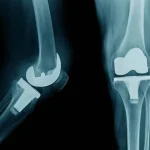

تعویض مفصل هر دو زانو همزمان به این معناست که جراح ارتوپد در یک عمل جراحی، هر دو مفصل زانو را با پروتزهای مصنوعی جایگزین میکند. این روش معمولاً برای بیمارانی توصیه میشود که هر دو زانوی آنها به شدت دچار آرتروز یا آسیبهای مفصلی شده باشد و درد و محدودیت حرکتی شدیدی داشته باشند.

انجام این جراحی بهصورت همزمان میتواند باعث کاهش زمان کلی درمان و بهبودی شود، زیرا بیمار تنها یک دوره بستری در بیمارستان و یک دوره توانبخشی را تجربه میکند.

با این حال، تعویض همزمان هر دو زانو چالشهایی نیز دارد، از جمله دوره نقاهت دشوارتر و نیاز به قدرت جسمانی بالاتر برای تحمل روند بهبود. این روش معمولاً برای بیمارانی که از سلامت عمومی خوبی برخوردارند و توانایی تحمل جراحی طولانیتر را دارند، پیشنهاد میشود.

جراحی خاص تعویض همزمان مفصل هر دو زانو و اصلاح پای پرانتزی، توسط دکتر حاجی خانی با موفقیت انجام شد. این عمل، یکی از جراحیهای پیچیده و دشوار در حوزه ارتوپدی محسوب میشود که نیاز به مهارت، دقت بالا و تجربهی گسترده دارد.